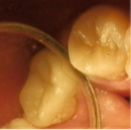

Paciente de sexo masculino de 23 años, con piezas 27 y 28 con caries profunda, ecosistema cerrado y cámaras amplias en análisis clínico radiográfico (figs. 4a,b). Se plantea tratamiento conservador en 27 y extracción en 28 ya que no ocluye con antagonista. En 27 se abre esmalte socavado, se elimina con cucharita la dentina necrótica reblandecida superficial, constatando ligera sensibilidad sin comunicación. En el análisis dentinario se observa dentina de color amarillo, blanda y húmeda, o sea con las características de una caries muy activa (Fig 4c).